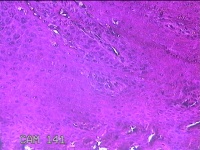

左侧足底结节

性别

男

年龄

49岁

临床诊断

鸡眼

一般病史

发现左侧足底结节伴隐痛不适1年余。

标本名称

大体所见

灰白粉红色带皮肤样结节1x0.7x0.2cm一个,表面糜烂,切开结节呈实性,切面灰白粉红色,质硬。